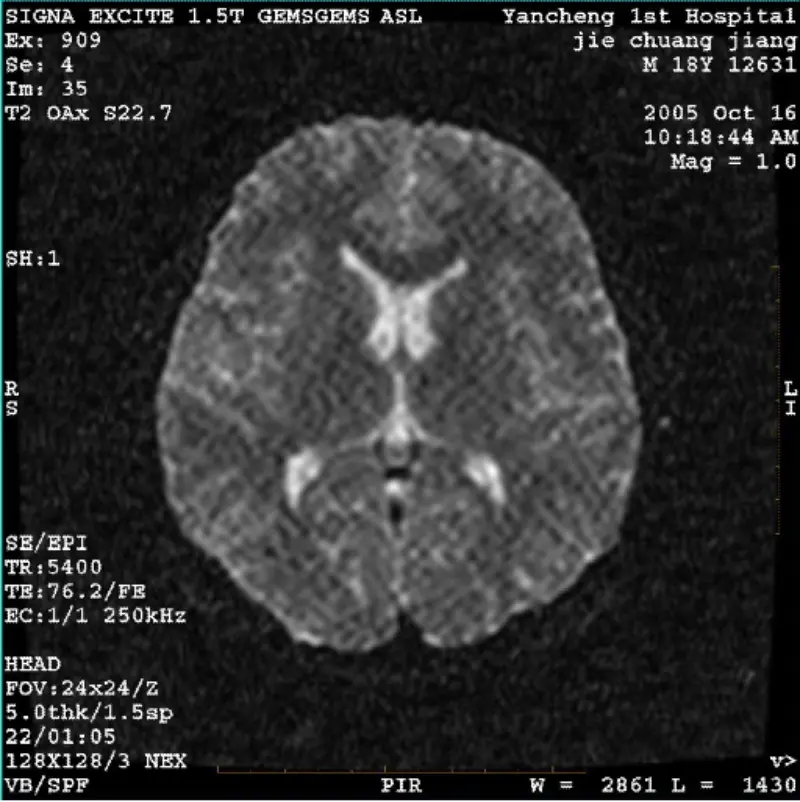

Per saperne di piùSISTEMA: 1.5T Signa Twin Excite II (versione software 11.0M4) PROBLEMA/SINTO Immagini DWI (modalità Zoom e modalità intera) e Fiesta (modalità zoom e modalità intera). artefatto reticolato o di velluto a coste visibile, indipendentemente dall'uso della bobina per il corpo o della testa bobina......